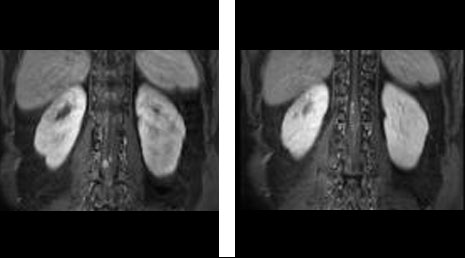

55. Spinal metastasis- adrenal